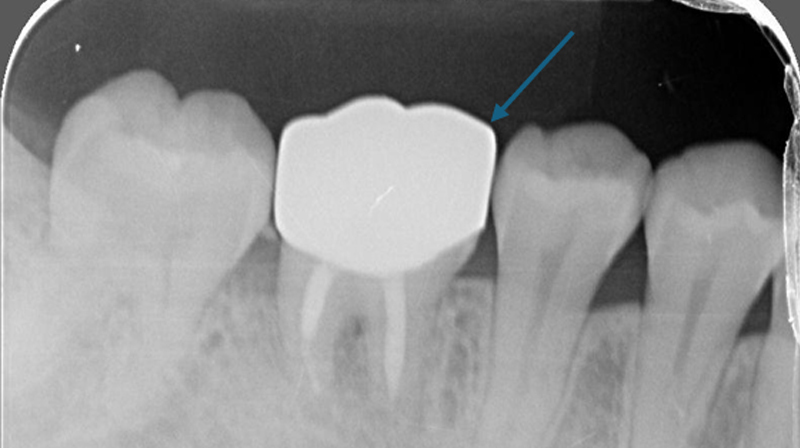

術前評估口腔狀況

右下第一大臼齒斷裂

術前